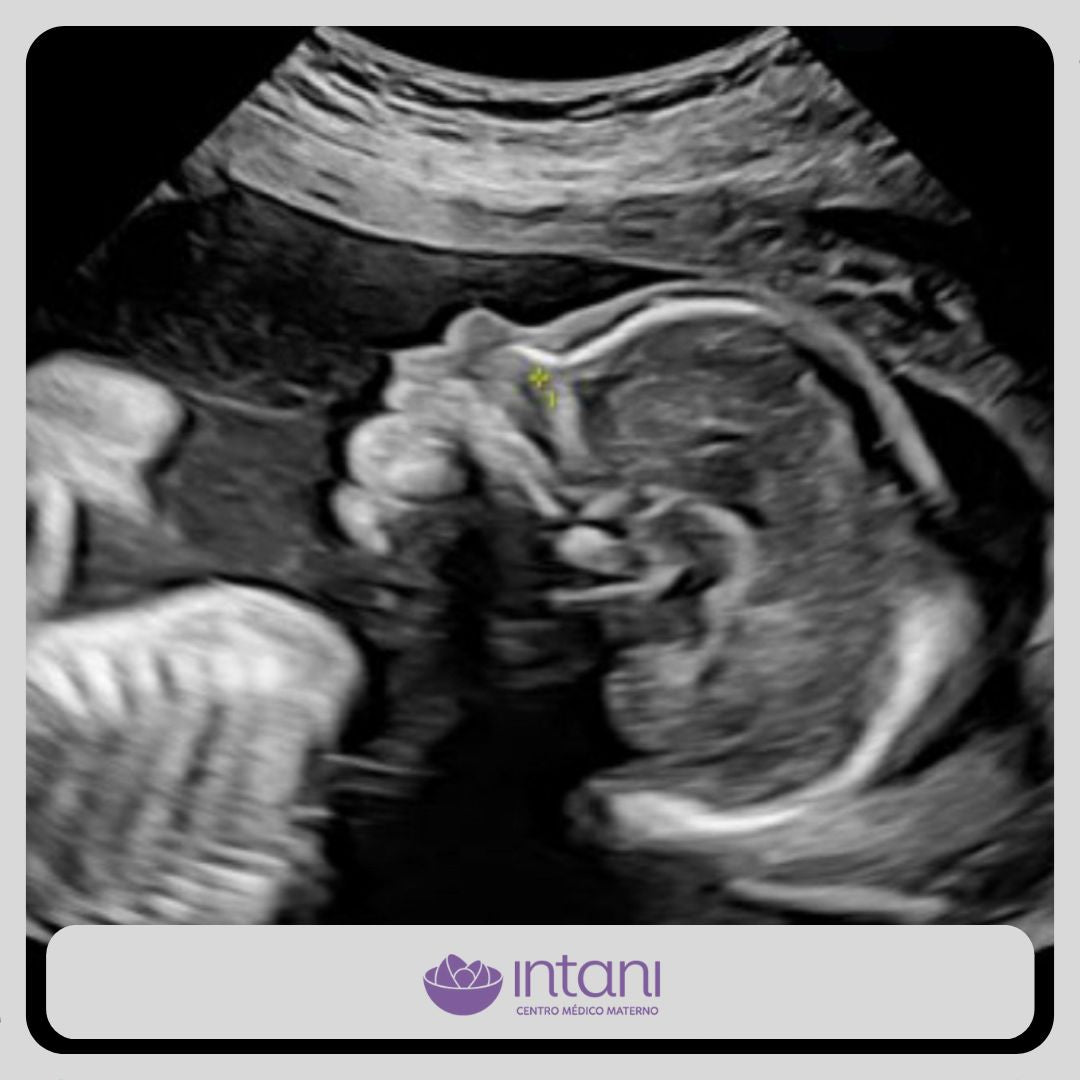

Realizarlo ideal entre las 20 a 24 semanas.

Una de las ecografías más importantes del embarazo. Este es el momento para descartar anomalías fetales de órganos, sistemas y evaluar la circulación placentaria.